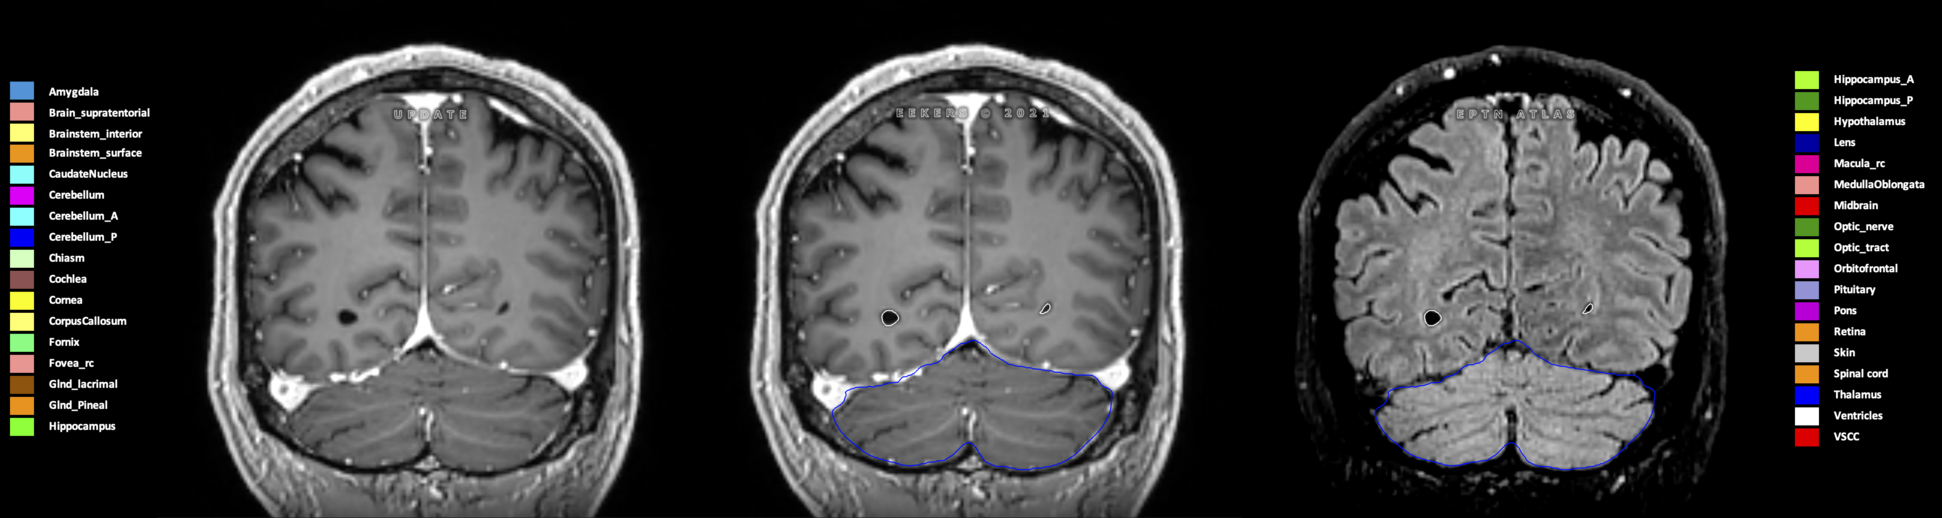

Eekers et al. have published an international neurological atlas for contouring of organs at risk in consensus with the European Particle Therapy Network (EPTN) in 2018 and an update in 2021. The purpose of this consensus atlas is to decrease inter- and intra-observer variability in delineating OARs relevant for neuro-oncology.

Included are all OARs known to be relevant for radiation-induced toxicity in neuro-oncology: brain, brainstem (midbrain, pons, medulla oblongata), chiasm, cerebellum (anterior & posterior), cochlea, cornea, hippocampus (anterior & posterior), hypothalamus, lens, lacrimal gland, optic nerve, pituitary, skin, and vestibular & semicircular canals. To further facilitate research on cognition, vision and radiological changes after irradiation of the brain, potential clinically-relevant OARs are included: amygdala, caudate nucleus, cerebellum (anterior & posterior), corpus callosum, fornix, macula, optic tract, orbitofrontal cortex, periventricular space (PVS), pineal gland, and thalamus.

Three-dimensional delineation of the 25 consensus OARs for neuro-oncology are shown on CT (WW/WL 120/40, 3000/600), 3T MR images, (T1Gd, T2FLAIR 1mm) and 7T MR (MP2RAGE 0.7 mm). All are presented in transversal, sagittal and coronal view.